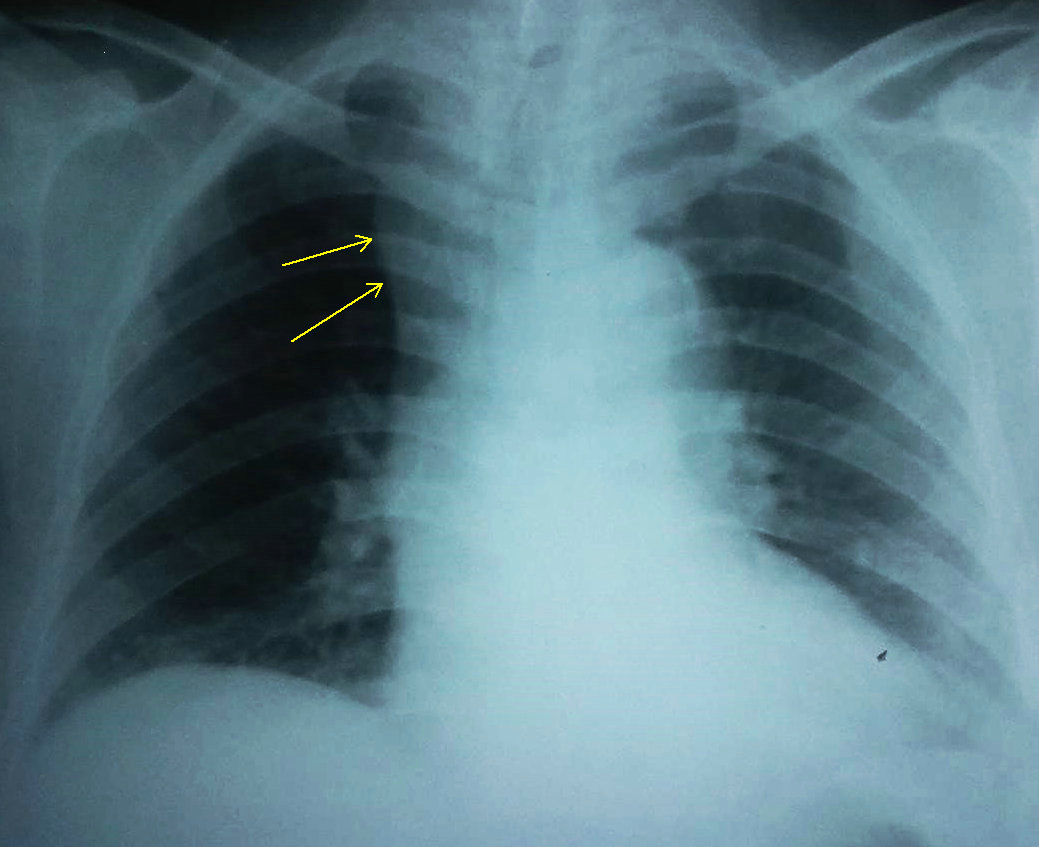

女,70,脑梗塞住院体检。箭头所指是上腔静脉吗?

不是孤立突入胸腔内阴影,而是下缘一直延续下来,是上腔静脉影。年龄较大,有高血压病史患者,一般上腔静脉影较宽。

不是上腔静脉影,因为气管捎右牵拉右移位,边缘清晰,外侧缘似有类三角形改变,有上肺透亮度增高,结合有脑梗塞病史,不除外肺梗死或肺不张。建议ct增强

老年人无名动脉可能性大,也可能是上腔